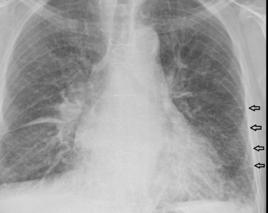

克利B線

位於肺周邊、水平的短線(通常小於1 cm)。克利B線即肺小葉中膈(interlobular septa)通常會與肋膜相接。B線可能出現於肺的任何區域,但最常見的地方是在肋橫膈角的位置。